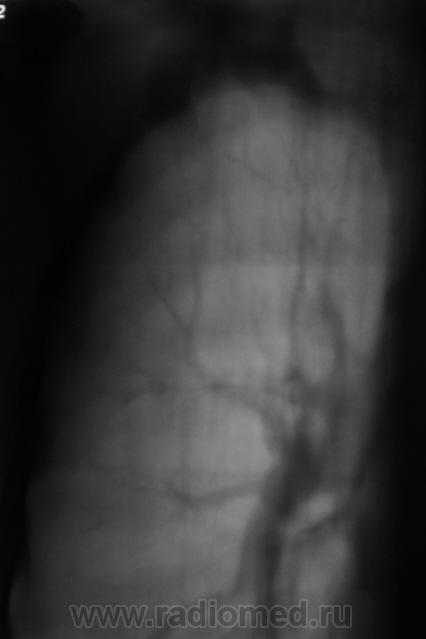

1. срез.

2 срез

3 срез

А, эти тени, тоже можно отнести к "тубарским"?

А во что же их еще определить? По ходу диференцировать с мальформациями ...нижняя на какого то "крабика" смахивает...хотя это еще ничего не значит...

Такое ощущение, что он свой ТБС уже пережил, возможно на ногах. Иногда фтизиатры пользуются термином - самоизлеченный ТБС ( возможно чуть по другому). А вот те тенюшки в левом легком - это то, что может вырасти в дальнейшем в какое-нибудь деонтологическое заболевание. Цепляться ли за них сейчас? Через год будет поздно. Мы такое уже проходили. И что-же делать?